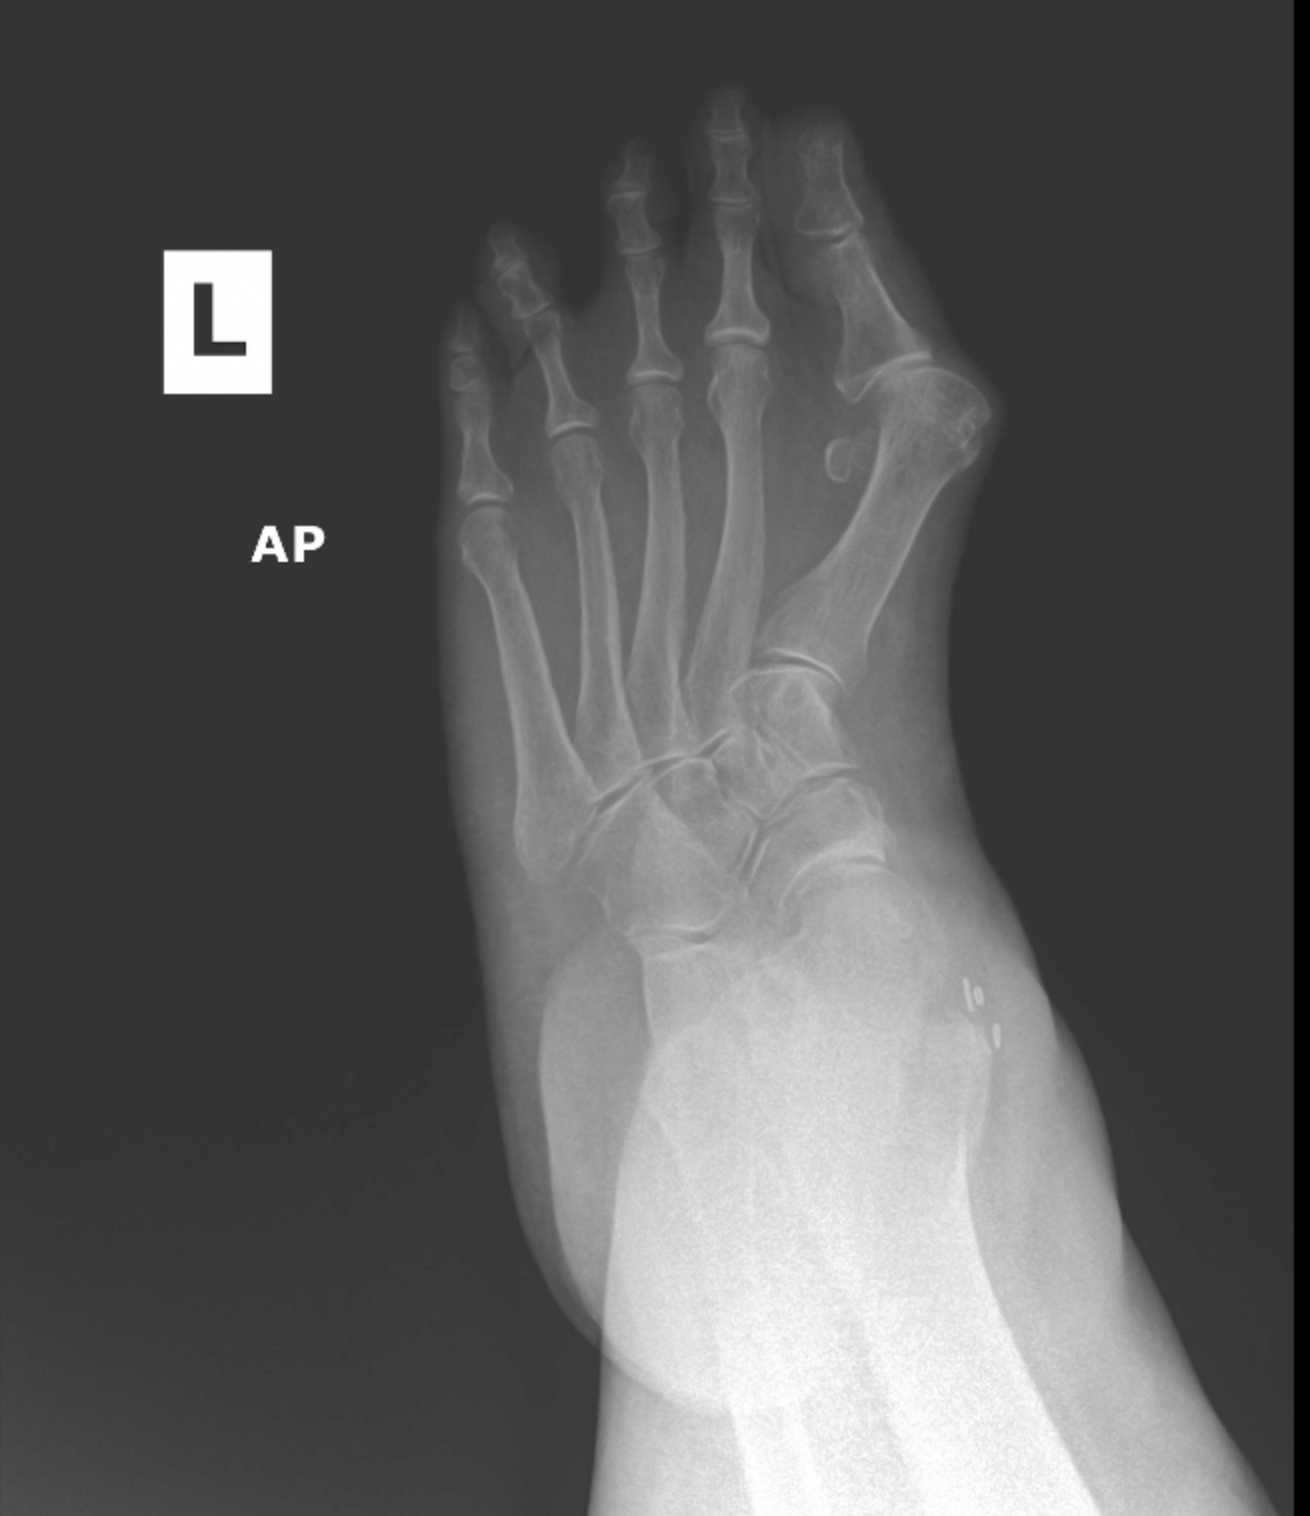

MIS Bunion

MIS3

MIS2